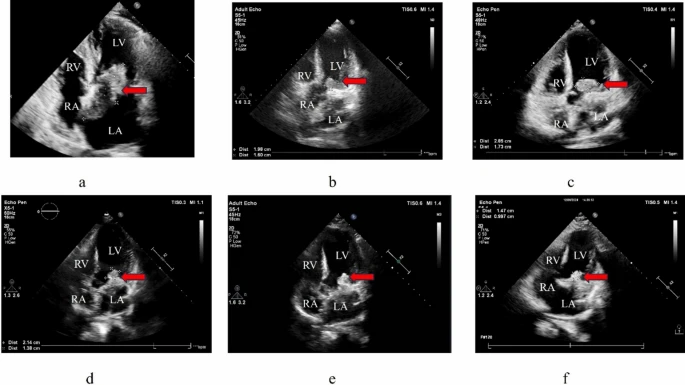

The transthoracic real-time three-dimensional echocardiography revealed an irregularly shaped, isoechoic mass in the left atrium of approximately 64 × 41 mm. The tumor was connected to both the interatrial septum and the base of the mitral valve annulus. It had well-defined borders and unequal internal echogenicity, with parts of the mass shifting between the left atrium and the left ventricle throughout the cardiac cycle. Contrast-enhanced chest CT revealed a hypodense lesion in the left atrium (54 × 43 mm) with septations and modest elevation, partially extending into the left ventricle. Upon admission, tumor markers carcinoembryonic antigen (CEA) (10.48 ng/mL), neuron-specific enolase (NSE) (38.71 ng/mL), and cancer antigen 125 (CA125) (182.97 U/mL) were all elevated.

The procedure went smoothly, and the patient made a full recovery after more than two weeks in the hospital. Symptoms such as chest tightness and dyspnea were relieved after surgery. A recurrence occurred 31 days after surgery, and echocardiography detected a mass in the left ventricle (19.8 × 16 mm). Genetic tests found amplification of the MDM2 gene, which is typically linked to sarcomas. Given the disease’s fast clinical progress, the patient was started on liposomal doxorubicin at a dose of 40 mg, delivered as a 16-hour continuous intravenous infusion using an electronic pump. The treatment protocol was repeated every 21 days. The patient underwent three cycles of liposomal doxorubicin as first-line treatment.

After three cycles of treatment, follow-up echocardiography revealed a mass growth to 28.5 × 17.3 mm. The patient experienced leukopenia and fatigue during chemotherapy, improved with granulocyte colony-stimulating factor (G-CSF). Subsequently, anlotinib (10 mg daily) was given, leading to a reduction in mass size to 21.4 × 13.8 mm over several months, without notable adverse reactions. By November 2024, echocardiography indicated tumor progression with enlargement of the left atrium and ventricle, plus new mass-like lesions around the mitral valve orifice, measuring approximately 24 × 22 mm.